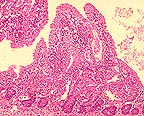

死亡動物からの組織の顕微鏡検査は、ウイルス性腸炎に一致しています。特に、繊毛先端に腸細胞の壊死があります。陰カは中等度から顕著に過形成性です。中等度から重度リンパ形質細胞の浸潤物と種々程度の繊毛萎縮、鈍化、融合、欠損がさらに長期の症例の腸に見られます。特徴的な腸の変化は感染後8ヶ月目に見られます。(原文ページの画像を参照ください)